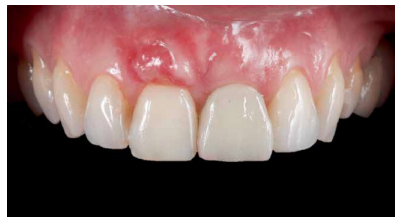

Se llevó a cabo una primera revisión del procedimiento quirúrgico a los 7 días. Se observó una correcta cicatrización inicial de los tejidos blandos y ausencia de patología infecciosa o inflamatoria (Figura 18). A los 14 días se realizó una segunda revisión en la que se retiró la sutura (Figura 19). La revisión al mes de la cirugía mostró una correcta estabilidad inicial de los tejidos blandos y duros, así como la ausencia de signos relacionados con el fracaso del procedimiento (Figura 20).

A los 4 meses se evidenció una correcta estabilidad del IOI fruto de un correcto proceso de osteointegración. Respecto a los tejidos blandos, se podía observar una disminución del volumen de la papila interdental (Figura 21). Dada la ausencia de signos y síntomas y la correcta osteointegración del IOI, se realizó la modificación del perfil subcrítico con el fin mejorar la disposición del tejido blando gingival y favorecer la recuperación de dicha papila (Figuras 22 y 23).